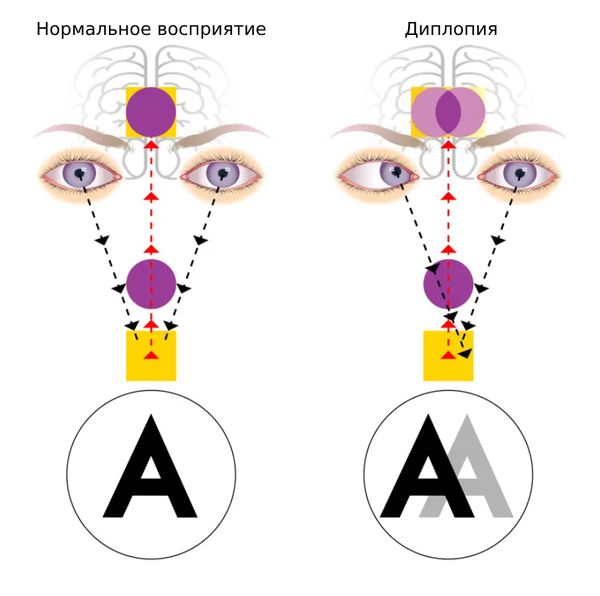

Диплопия (Diplopia) — это нарушение зрения, при котором человек видит два изображения одного и того же объекта. Это может быть небольшое размытие с лёгким наложением картинок или чётко разделённые двойные изображения. Обычно диплопия появляется в результате проблем со зрением, глазодвигательными мышцами или нервами. Однако бывают и причины общего характера: отравления, инфекции, травмы или системные заболевания, поражающие несколько органов или весь организм.

Нормальное зрение и диплопия

В зависимости от проявлений выделяют монокулярную и бинокулярную диплопию. При бинокулярной человек чётко видит два изображения одного и того же предмета, а при монокулярной — двойной контур одного объекта, тень от контура или размытое изображение.

Бинокулярная диплопия возникает при взгляде двумя глазами, но исчезает, когда человек смотрит одним. Она появляется из-за того, что свет попадает на сетчатку одного глаза не в центр, а в соседнюю зону, что вызывает ощущение двоения. Свет падает неправильно из-за смещения глазных яблок [3][4]. Причиной их смещения являются заболевания, при которых поражаются нервы и мышцы вокруг глаза, например паралич нервов, миастения и синдром Гийена — Барре. Эти заболевания нарушают движение глаз и/или вызывают косоглазие [5][6][7].